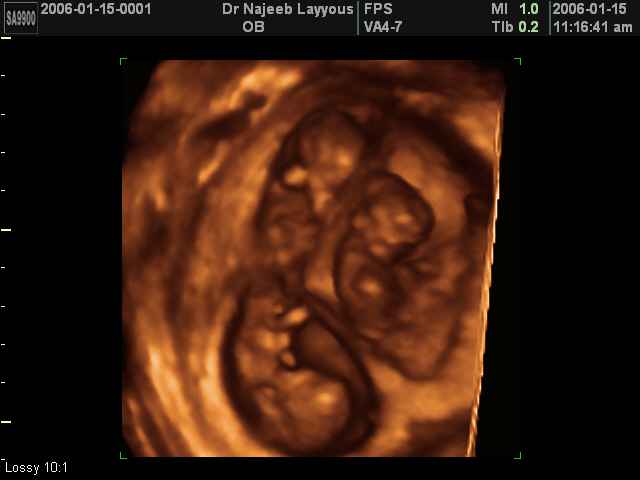

- صور لتوائم

صور لتوائم بجهاز الالتراساوند ثلاثي الأبعاد | الدكتور نجيب ليوس